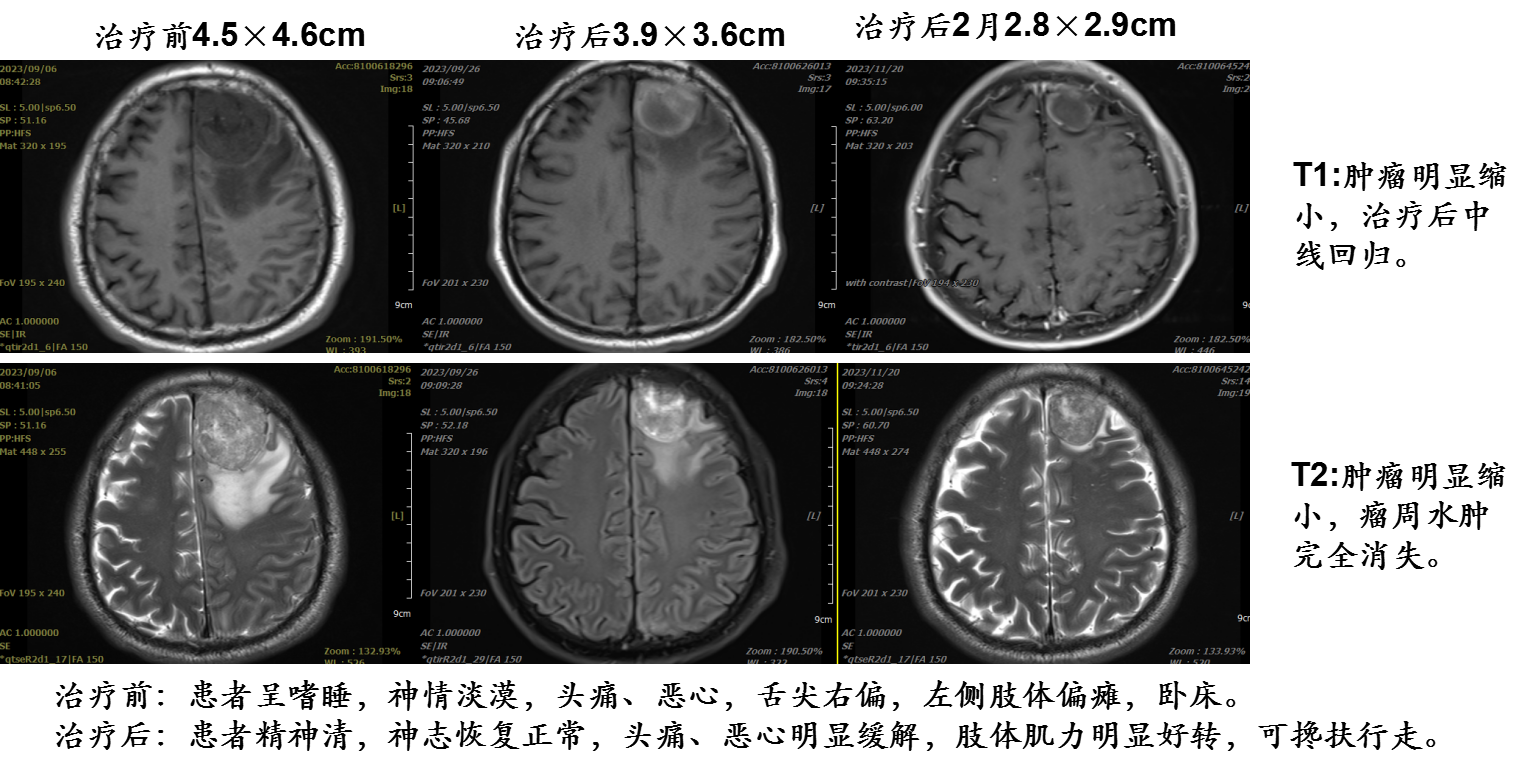

01 病例一

谢某某,男,52岁,湖南湘乡市;诊断:肺大细胞神经内分泌癌脑转移; cT2N2M1 IVB期;KPS评分:60分。

病例提供医生:杨钰玲 科室:放疗中心一科(国际一部)